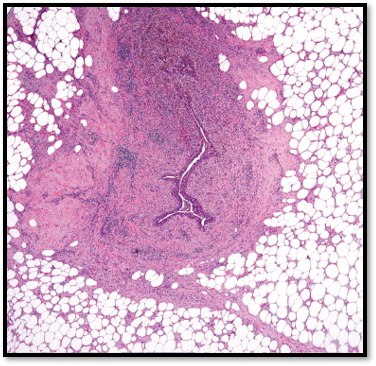

Gross: Bulbous protrusions

Microscopy: increased stromal cellularity and overgrowth –> leaflike architecture

Phyllodes Tumor